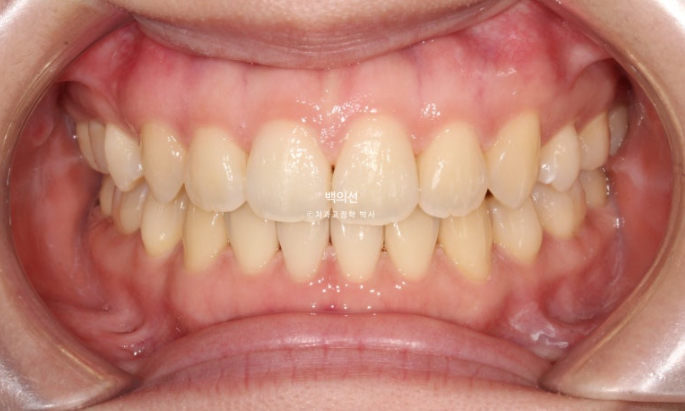

25.07

중심선은 정확히 맞으며

교합은 긴밀한 1급 교합관계가 보입니다.

남아있던 발치공간은 깔끔히 마무리 되었습니다.

맞아진 중심선과 개선된 앞니 개방교합. 이제 면 편하게 끊어 드실 수 있겠어요.